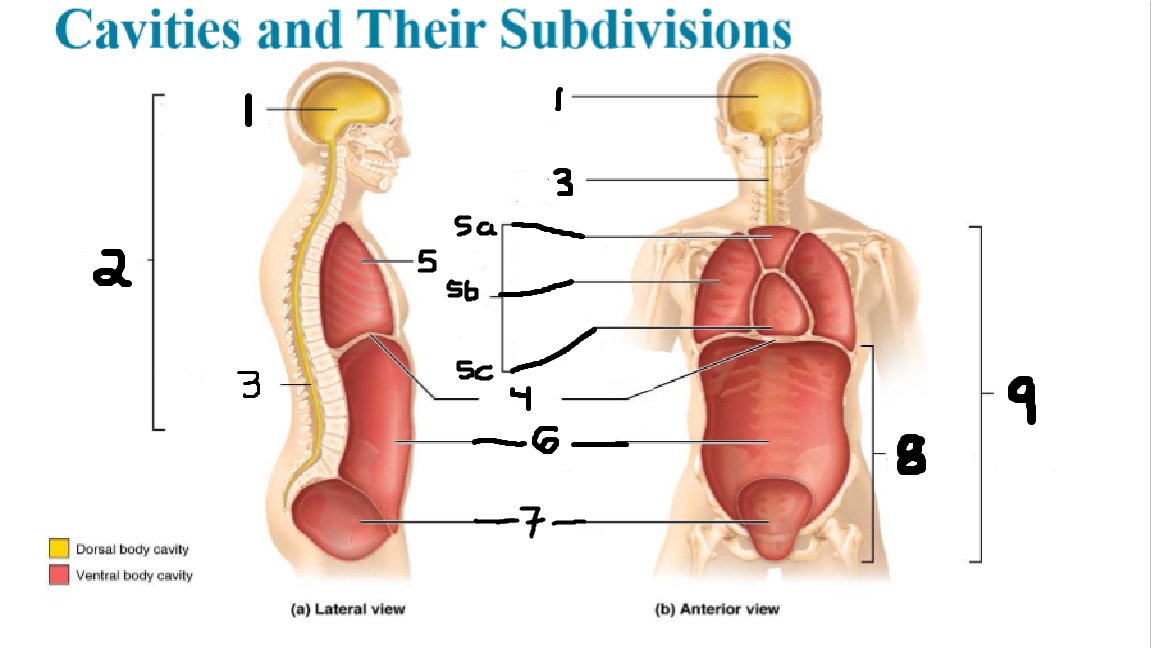

What cavities are part of the dorsal cavity?

The cranial and the Spinal (vertebral) cavities

What kind of cavity is labeled 2?

The dorsal body cavity (containing the cranial and spinal cavities)

What is the purpose of the dorsal cavity?

protects the nervous system

What is the main organ encased by the cranial cavity?

the brain

What cavity is labeled #1?

The cranial cavity

What is the main organ encased by the vertebral cavity?

the spinal cord

What is another word for the vertebral cavity?

the spinal cavity, or the spinal canal

What body cavity is labeled 3?

the vertebral cavity.

What cavities are included in the ventral cavity?

the thoracic, abdominal, and pelvic cavities.

What body cavity is labeled #6?

the abdominal cavity.

What are the main organs of the abdominal cavity?

the digestive organs such as the stomach, intestines, spleen and liver

What cavities are included in the Abdominopelvic cavity?

the abdominal cavity and the pelvic cavity

What body cavity is labeled #8?

The Abdominopelvic cavity

What does the diaphragm separate?

the thoracic and the abdominal cavities

What is labeled #4?

the diaphragm

What organs does the pelvic body cavity contain?

urinary/reproductive organs and rectum

What is labeled #7?

the pelvic cavity

What does the thoracic cavity encase?

the heart and the lungs

What is labeled #5?

the thoracic cavity

What part of the thoracic body cavity is labeled 5a?

superior mediastinum

What part of the thoracic body cavity is labeled 5b?

pleural cavity

What part of the thoracic body cavity is labeled 5c?

pericardial cavity within the mediastinum

What body cavity encloses the heart?

the pericardial cavity.